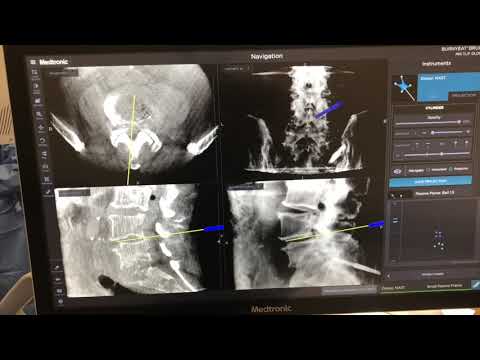

L4-5, L5-S1 MIS TLIF Reconstruction